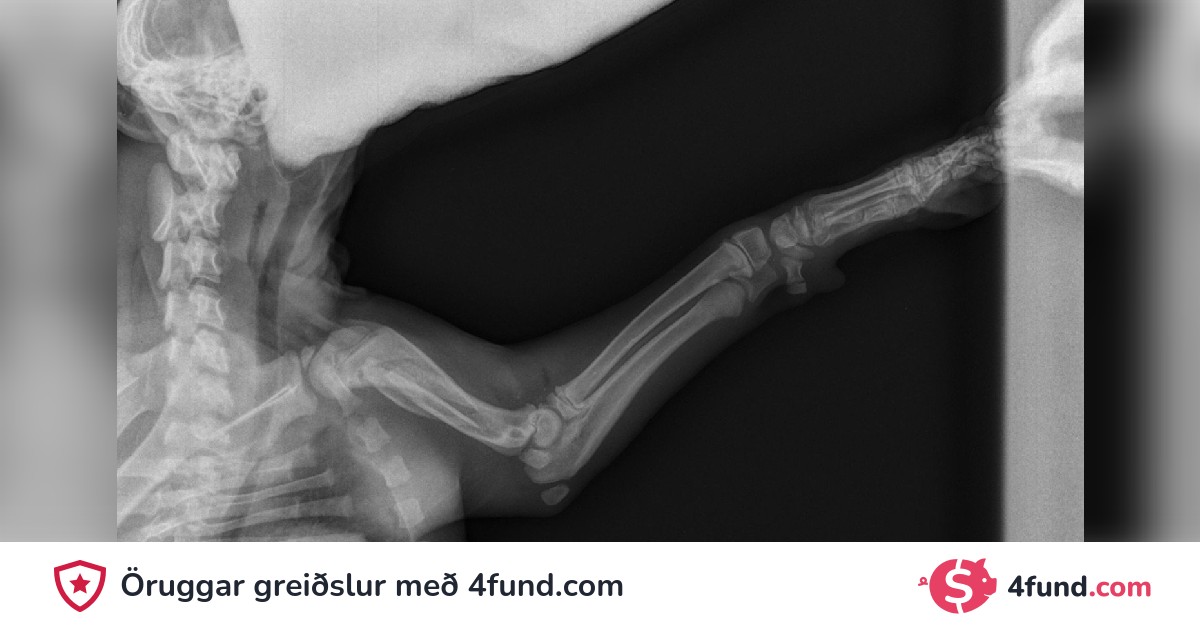

Aðgerð á brotnu upphandlegg

Góðan daginn, lítill hvolpur var ráðist á. Þeir báðu mig um 1400 auk virðisaukaskatts fyrir aðgerðina. Ég veit hvað ég þarf að gera, hún á á hættu að þurfa að aflima hana.